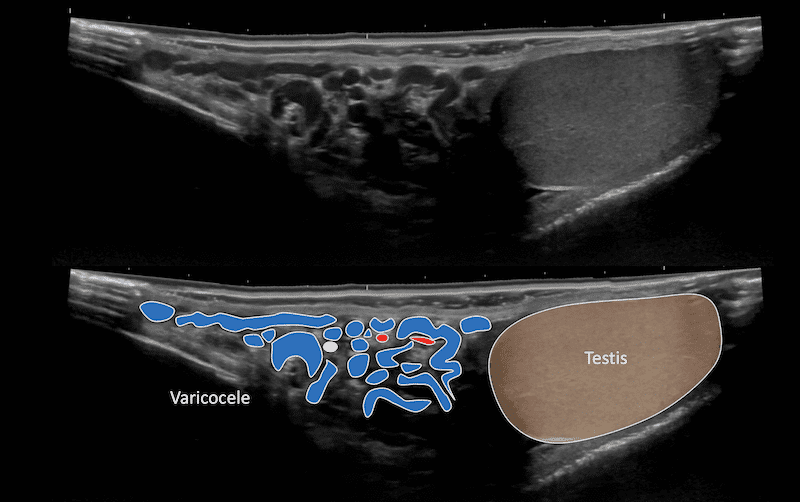

Immagine 1: Scansione dell’emiscroto sinistro dall’alto verso il basso lungo il cordone e poi attraverso il testicolo.

Vengono mostrate le vene anecoiche dilatate del plesso pampiniforme. Questo è un varicocele.